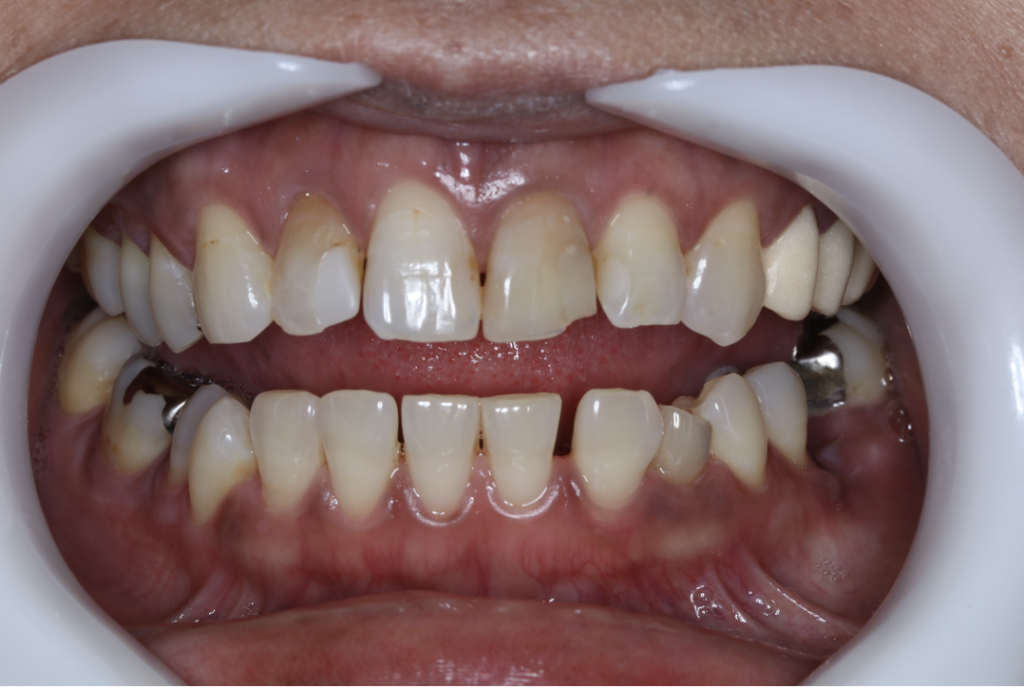

セラミック症例②

年齢 40代女性

治療期間 1ヶ月

治療内容 ジルコニア

治療箇所 右上6番

治療費用 100,000円